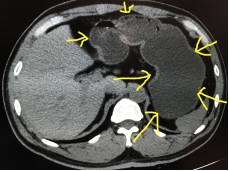

图6

图6:这是图4患者的图像,向肛门注入清水,整个结肠充盈了清水后,壁薄,显示得一览无遗。